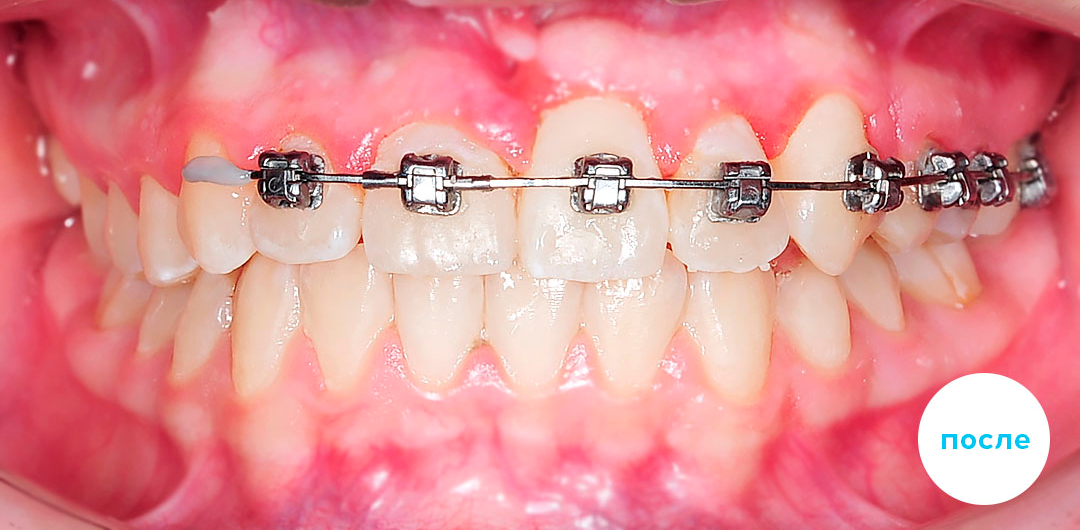

До

После

Лечение 3 класса с удалением 4х премоляров